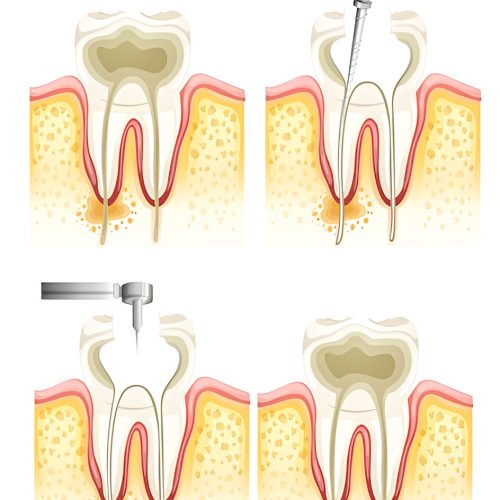

Deep Cleaning for Gum Disease

The performance of Scaling and Root planning functions to remove below-gumline plaque and tartar then makes root surfaces smooth for reducing regrowth.

Surgical Solutions

We perform flap surgery combined with bone grafting procedures to treat serious gum disease which helps maintain gum condition.